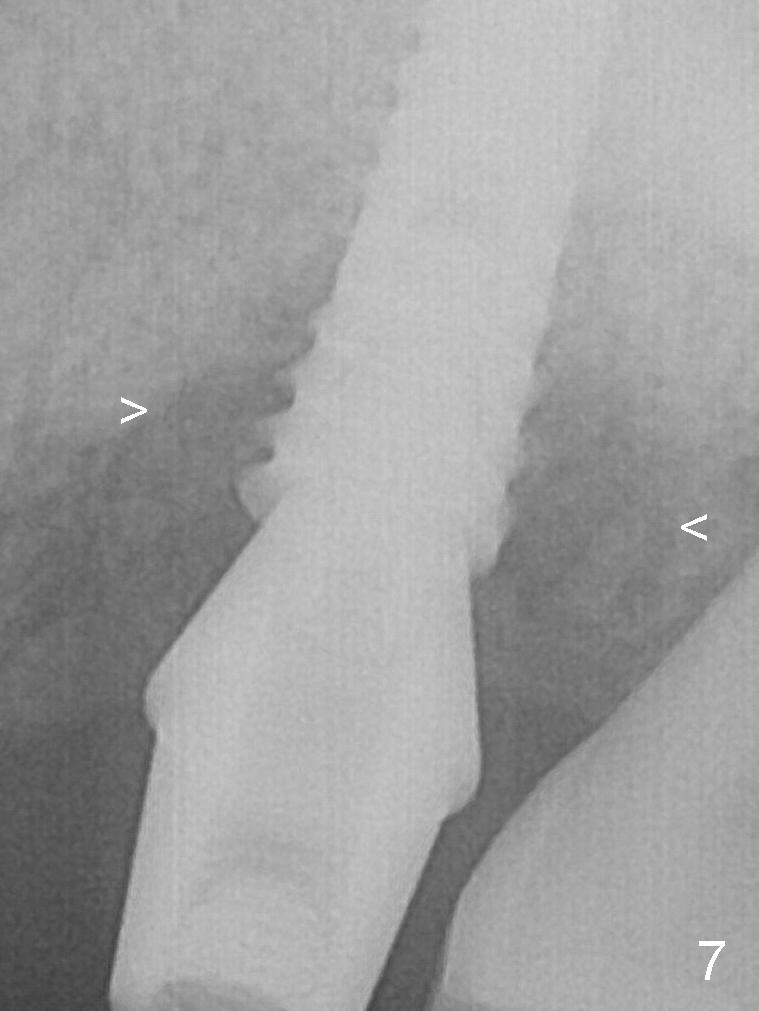

The amount of the bone graft mesial and distal the implant seems to reduce 3 and 4 months postop, respectively (Fig.6,7 arrowheads).  When the acrylic is cut off 4 months postop, the bone graft is loose.  The gingiva is unhealthy.  The abutment and implant are loose.  A healing abutment is placed (5x4 mm).